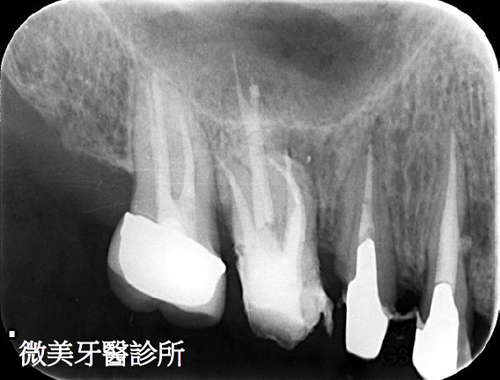

根管鈣化阻塞,利用顯微鏡搭配器械完成多根管治療

原先根管治療未完整,利用顯微鏡重新根管治療,達到多根管封填